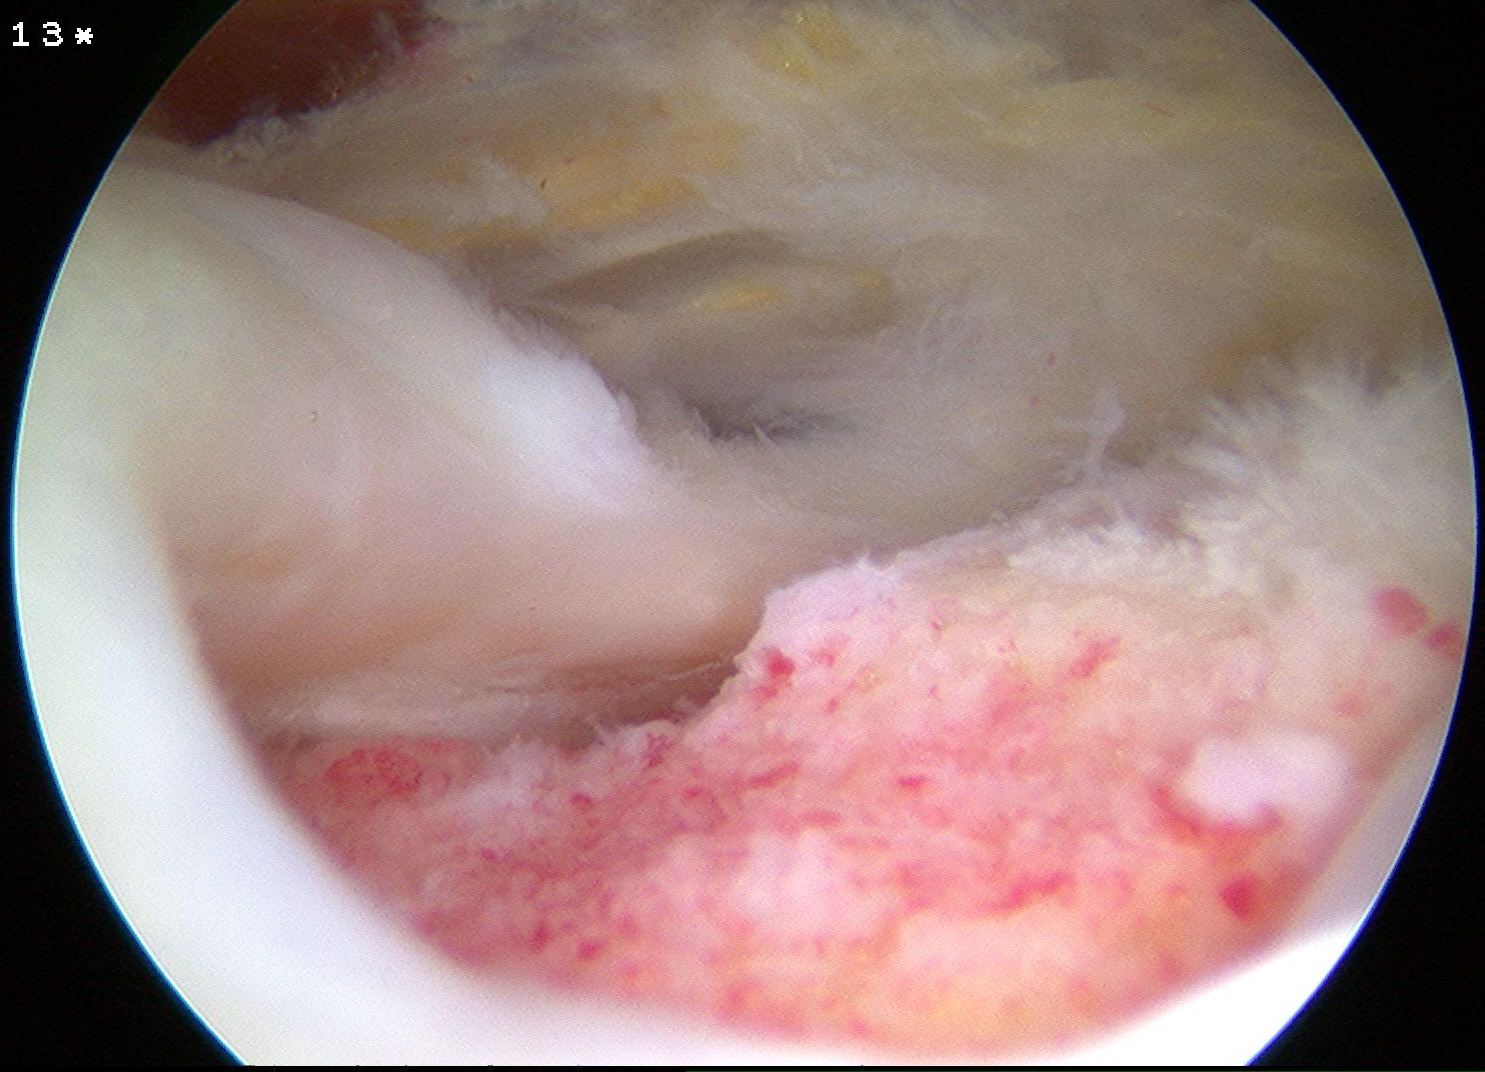

Bone marrow stimulation

Ajrawat et al JSES 2019

- systematic review of bone marrow stimulation of footprint

- K wire drilling of footprint / microfracture before RCR

- evidence that doing so decreases retear rate

- debride footprint to bleeding bone

- +/- microfracture / K wire of footprint / marrow stimulation